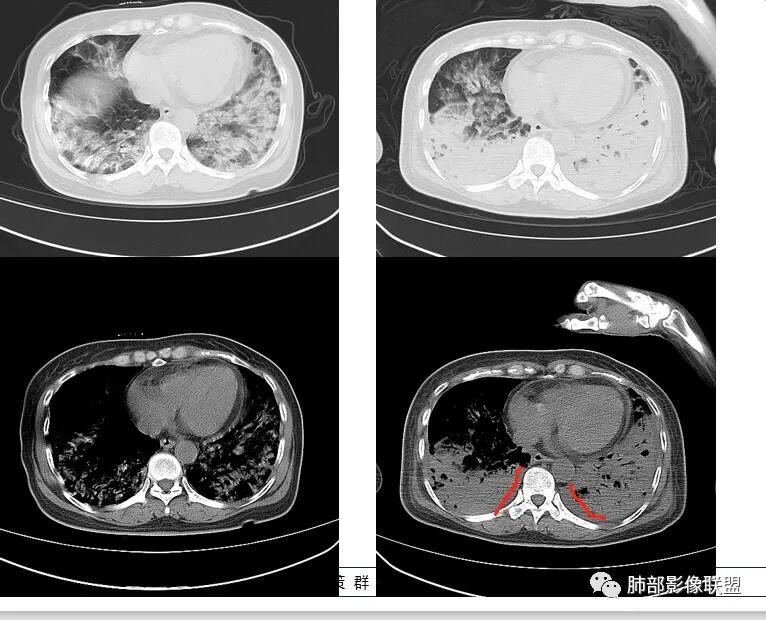

影像,第一次双肺中下叶胸膜下多发斑片状实变影,部分融合成,周围散发磨玻璃影,磨玻璃影内可见小叶间隔及小叶内间隔增厚,病变平行于胸膜,第二次间隔8天,双肺实变影明显进展,有重力作用,支气管近端堵塞,进展较快,临床有发热,血沉高,狼疮SLE阳性,考虑1:OP(机化性肺炎)2:SLE相关肺炎,建议支气管镜灌洗液病原学检测。

➢患者7天前起因受凉后出现阵发性咳嗽,无明显时间规律性,咳黄白粘痰,发热,体温最高达39.5℃,伴鼻塞、流清涕,。两肺下叶背段,后基底段为主的渗出性的病变,短时间内病变明显的增多,双侧胸腔积液,狼疮全套抗R0/SS检测阳性,考虑狼疮性肺损,机化性肺炎?鉴别结核

老年女性,咳嗽咳痰伴发热7天,白细胞不高,血沉快,降钙素原不高。其他化验未见明显异常,狼疮全套抗Ro/SSA阳性,双肺野靠近胸膜下磨玻璃实变影,支气管通畅,有充气征,沿胸膜下分布,有细网格征,7天后进展明显,实变影加重,胸膜肥厚,胸水不明显,心包少量积液?抗感染治疗无效,考虑非感染性疾病可能性大,结缔组织相关性肺病?狼疮性肺炎?机化性肺炎?鉴别病毒性肺炎。

老年女性,咳嗽咳痰发热7天。无气促。白细胞计数不高,PCT稍高,PPD(+),抗Ro/SSA阳性。CT:双肺野靠近胸膜下磨玻璃实变影,支气管通畅,有充气征,沿胸膜下分布,有细网格征。予抗生素治疗,8天后复查胸部CT见病灶范围扩大,实变影加重,胸膜肥厚,胸水不明显。抗感染治疗无效,考虑有:1.非感染性疾病:结缔组织相关性肺病,支持点:肺部CT表现为间质性炎症病变,抗RO/SSA(52)阳性;2.病毒性肺炎:患者无气促症状,可能性小;3.肺结核。

第一次双肺中下叶胸膜下多发斑片状磨玻璃及实变影,病变平行于胸膜,支气管通畅,8天后,双肺实变影明显进展范围扩大,部分支气管近端堵塞,进展较快,胸腔积液,抗感染治疗无效,考虑:非感染性疾病:结缔组织相关性肺病。鉴别机化性肺炎。

外围胸膜下,实变+GGO+网格,支气管通畅

提示间质为主病变

进展迅速——肿瘤就不用考虑,考虑炎性病变

2、非感染:OP类病变——红斑狼疮?

因为间质纤维化类病变引起实变的:OP、AIP